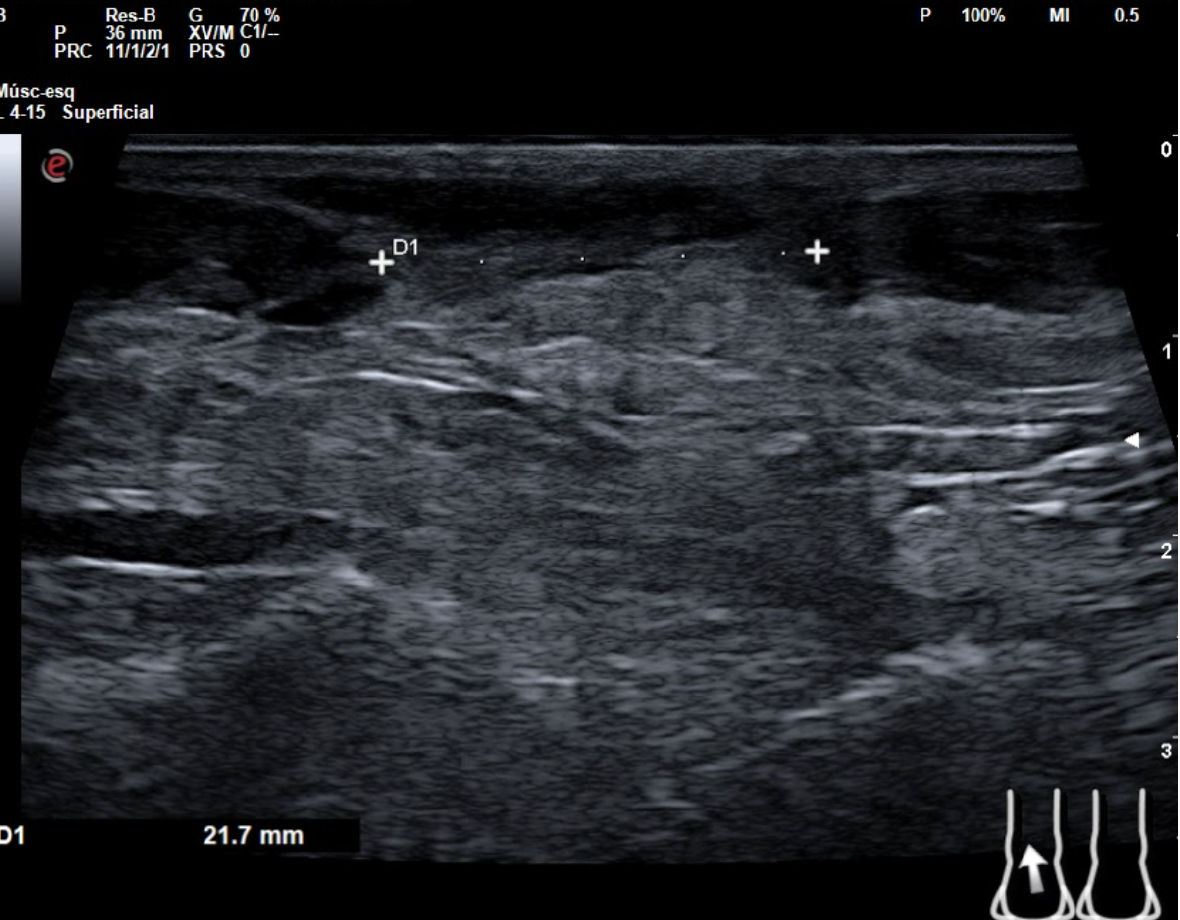

Hallazgos ecográficos

En tendón aquíleo izquierdo se aprecia rotura completa con solución de continuidad de 2 cm localizada a 5,7 cm de su inserción en el calcáneo. Presenta áreas hipoecoicas peritendón que sugieren hematoma secundario. En el aquíleo derecho presenta leve hipoecogenicidad y engrosamiento del tendón sin solución de continuidad que sugiere tendinosis. Importante componente inflamatorio. No datos de TVP. Poplítea y safena externa permeables y compresibles en ambas extremiedades.

Juicio clínico: Rotura completa de tendón de Aquiles izquierdo. Tendinosis aquílea derecha.